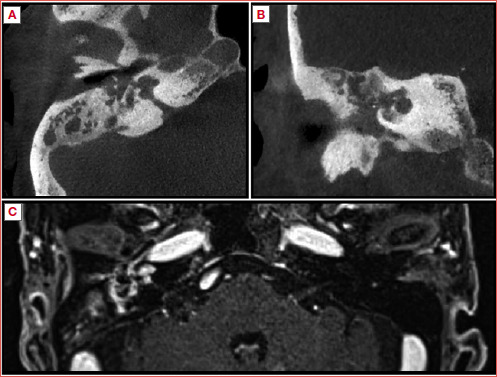

Results: Among 610 patients with antineutrophil cytoplasmic antibody-associated vasculitis (AAV) diagnosed and followed at our Institution, 6 (0.8%) presented with exclusive ear involvement as first presentation, all affected by GPA. Most frequently patients presented with otitis media with effusion, sensorineural or mixed hearing loss, and dizziness. Two patients developed systemic symptoms. All patients experienced at least a partial recovery of middle ear function after starting immunosuppressive therapy.

Conclusions: AAVs rarely show initial presentation as isolated ear involvement, and more commonly present as otitis media with hearing loss that is unresponsive to conventional therapy. Once an AAV is suspected, surgery should be avoided since further damage can be caused by local iatrogenic inflammation sustained by the underlying condition. Local improvement is generally seen after the start of immunosuppressive therapy.